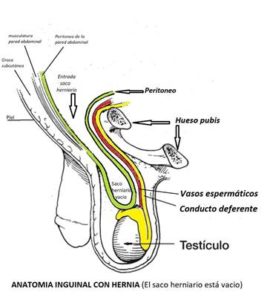

En el caso de la hernia inguinal, el fallo se produce en el llamado anillo inguinal, que por excesiva debilidad y laxitud en la zona, se acaba dilatando en exceso y permite la salida de la hernia.

De manera natural en el varón, por el anillo inguinal salen del abdomen unos conductos que se dirigen al testículo. Los vasos espermáticos y el conducto deferente.

De manera natural en el varón, por el anillo inguinal salen del abdomen unos conductos que se dirigen al testículo. Los vasos espermáticos y el conducto deferente.

Al dilatarse excesivamente el anillo inguinal profundo, junto a esas estructuras anatómicas descritas, se intruce también la membrana peritoneal también llamado peritoneo, que se convierte en el llamado saco herniario formando lo que llamamos hernia inguinal.

Al dilatarse excesivamente el anillo inguinal profundo, junto a esas estructuras anatómicas descritas, se intruce también la membrana peritoneal también llamado peritoneo, que se convierte en el llamado saco herniario formando lo que llamamos hernia inguinal.